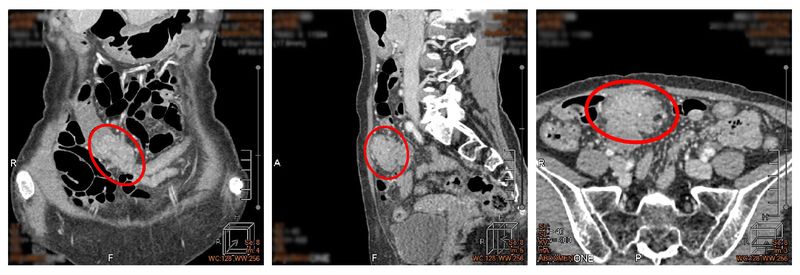

62歲王女士,無家族病史,不菸不酒、飲食清淡,平日也很注意健康,曾於五年前門診發現1顆 2 mm及1顆 5 mm的瘜肉,但未進行追蹤檢查,加上新冠疫情考量也遲未就醫。今年5月開始,王小姐下腹持續有鼓脹感,直到8月初安排健康檢查,結果在橫結腸發現異常腫塊,並已造成腸腔環狀狹窄,內視鏡無法插入狹窄後方,後經切片診斷為大腸癌,目前已安排治療中。

▲在橫結腸發現異常腫塊,經切片診斷為大腸癌